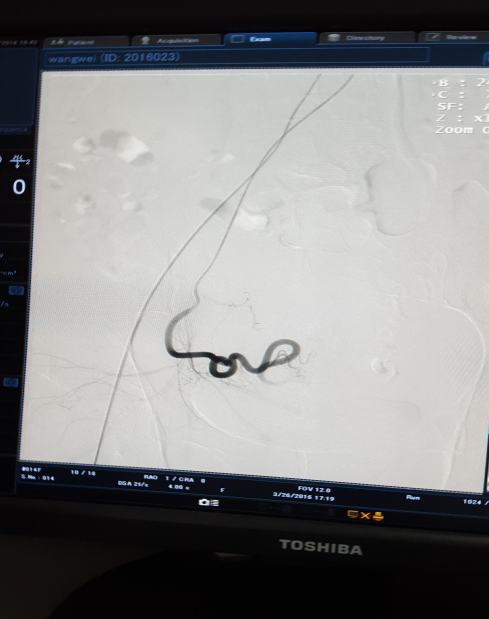

3月28日下午3点,在医院新导管室内,放射介入科主任张敏荣与任长德、李可峰医师成功地完成了新导管室建成后首例子宫腺肌症介入手术。该患者女性、40岁,因患子宫腺肌症,造成腹痛难耐,C臂下造影见:左子宫动脉增粗,分支数量增多、迂曲,用PVA颗粒栓塞迂曲的分支动脉,在妇产科保驾下,手术操作顺利。经过几天的对症治疗,各项检查指标符合出院标准,现病人已出院家中休养。该项手术的成功开展,又一次填补了市中医院该项之空白。